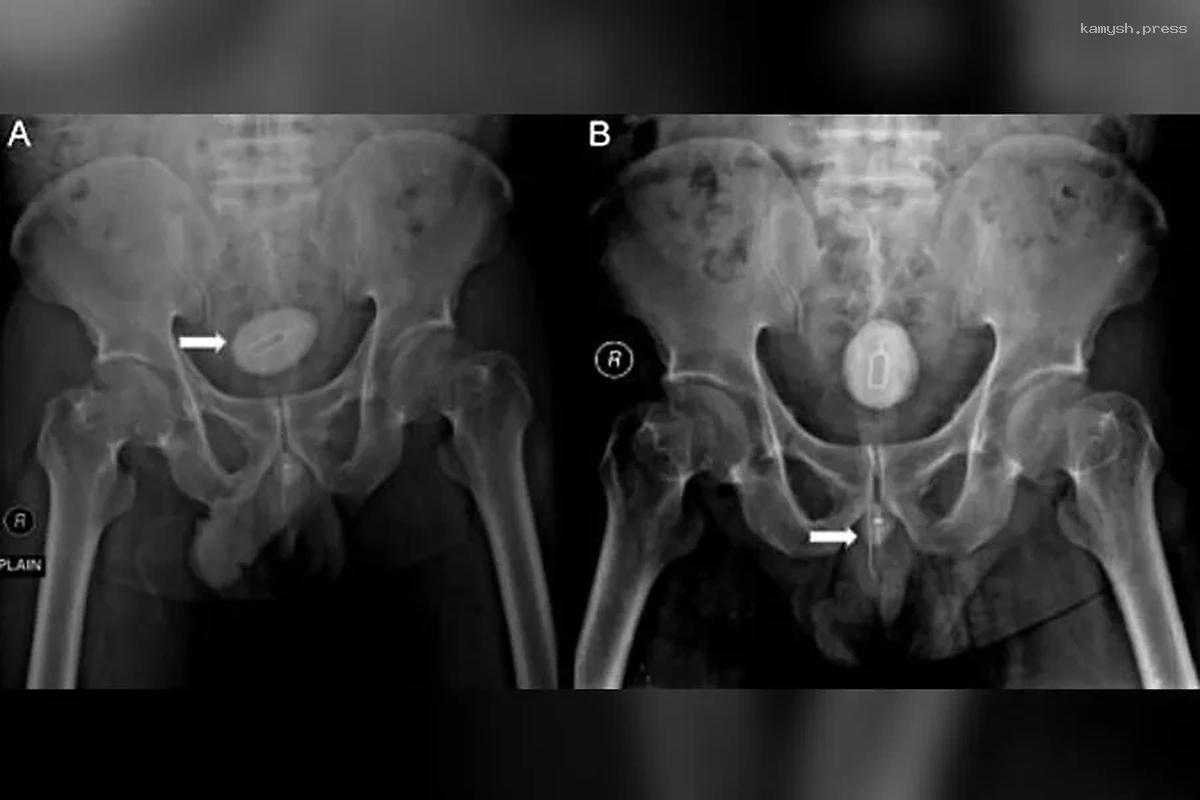

Снимки показали, что в уретре пациента были 10-сантиметровый кусок электрического кабеля, устройство для извлечения сим-карты из смартфона, игла длиной восемь сантиметров, обёрнутая канцелярской резинкой.